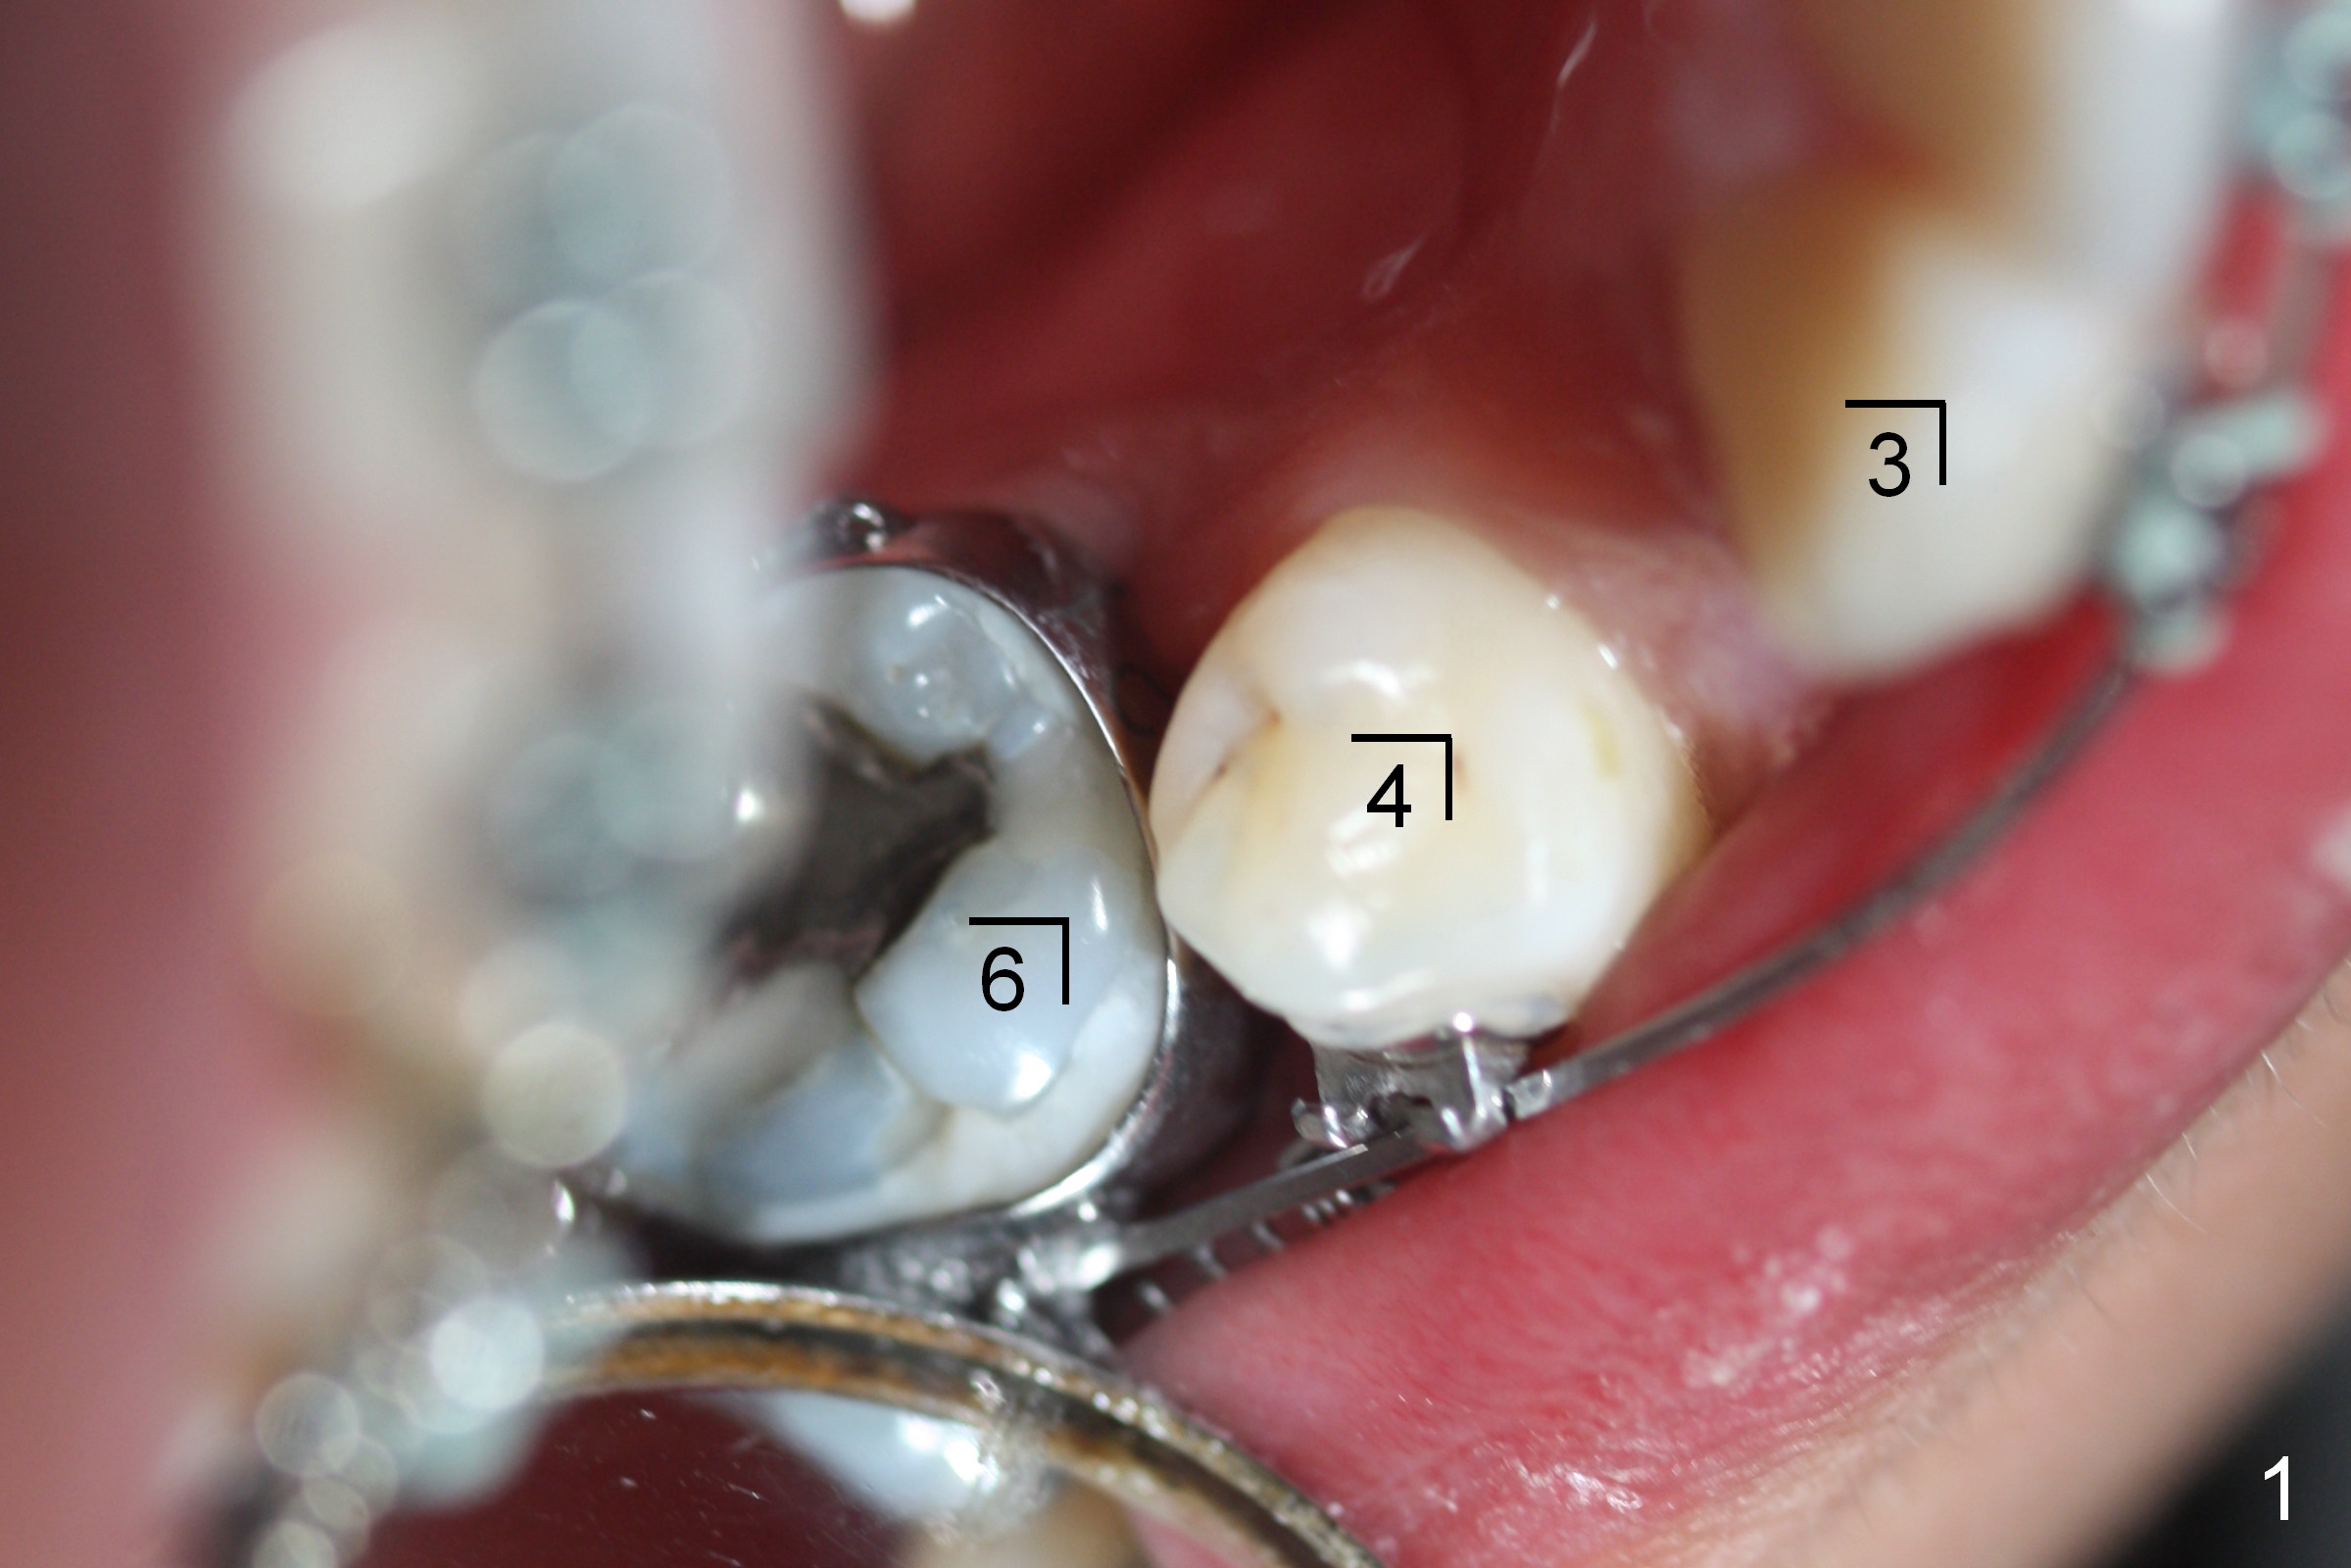

LR4 (Fig.1) and LL3 (Fig.2,3) are distalized 7.5 months of ortho treatment (1,2). Next step is to retract LR3 with closed coil spring (Fig.4) and de-rotate LL3 with a rotation wedge (Fig.5 *). The upper arch appears to be slightly in cross bite (Fig.4) 2 months after closed coil springs placed between the upper posted wire (<) and mini-implants (placed in the buccal tuberosity). Profile needs to be improved (Fig.6,7).